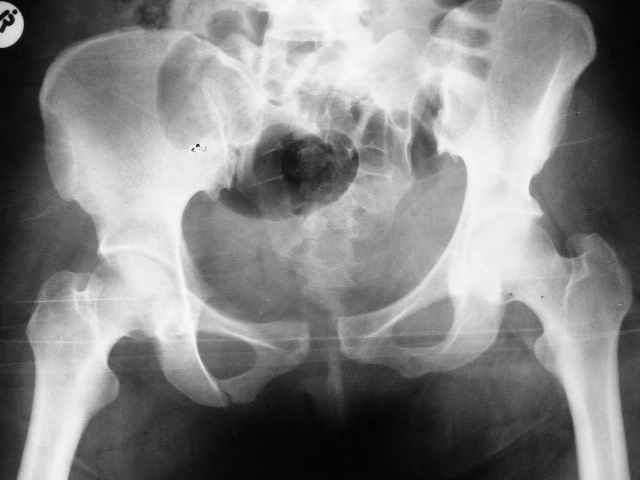

Больная 28 лет от роду попала в ДТП 12.12.04Что бы вы предложили.заранее признателен,Евгений И Чекашкин

У нас бы аппаратом все вправили, потом ввели закрыто винты через крестцово-подвздошное, а сперелди - пластину.

Сегодня утром прооперировал: на симфиз пластину на 4 винтах и два 6.5 мм винта с неполной резьбой на левое крестцово подвздошное сочленение. (пришлось открыть - девушка весьма внушительной комплекции и пропальпировать крыло и ости не представлялось возможным, спасительного в таких случаях набора канюлированных винтов в госпитале нет). Проконтролировал качество репозиции ЭОПом - остался доволен.

При таких переломах я применил бы ургентно в первый же день поступления переднюю фиксацию таза, хотя спереди, но создастся относительная стабилизация таза.

Наружный фиксатор на уровне spina anterior inferior в месте прикрепления прямой головки четырехглавой, где хорошая масса кости, провожу стержень под углом в направлении sciatic notch, который фиксируется дуговым стержнем, как на снимке, но возможны и другие различные варианты.

С первого дня создается стабильность таза, дает время на обдумывание плана, затем при желании перевод к передней фиксации пластиной, а потом только перкутанный метод фиксацию rрестцово-подвздошного сочленения.